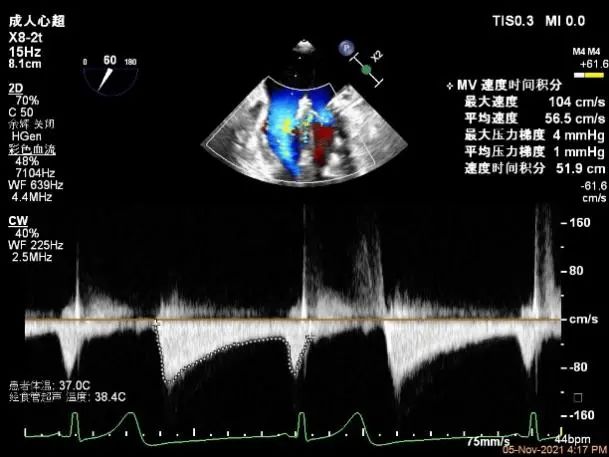

术前超声诊断

二尖瓣瓣环前后径26mm,左右径26mm

Bicom:MR(重度),返流束宽12.5mm,返流面积11.4cm²

PISA法定量EROA:0.74cm²,Rvol:118ml,RF:63%

右上肺静脉血流频谱呈收缩期反向

二尖瓣口平均跨瓣压差:4mmHg